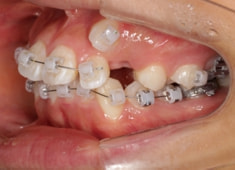

治療開始から11ヶ月後